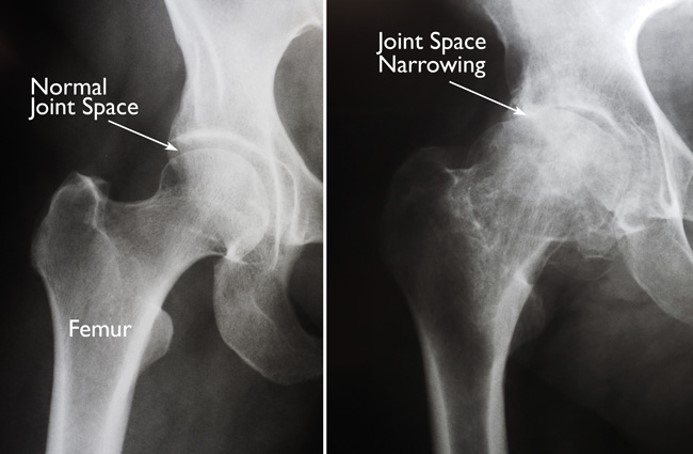

These two x-rays show the difference between a healthy hip joint on the left, and a narrowed and worn hip joint on the right.

X-Rays of Hip Joints